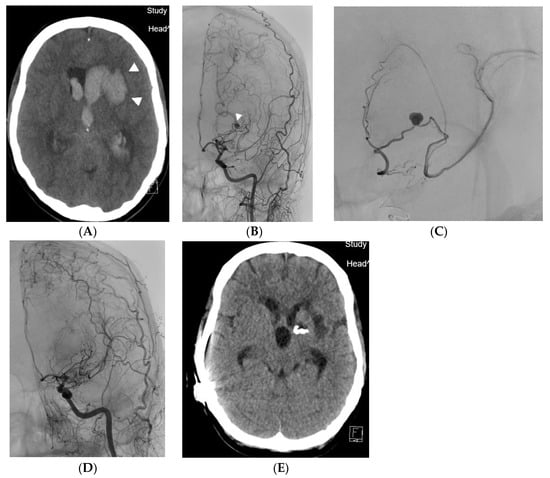

A 45-year-old female patient was admitted to the primary stroke center with sudden onset of headache, followed by somnolence and unconsciousness. The patient had a history of frequent migraines. CT scan showed a four-ventricle hematocephalus caused by a 27 × 31 × 17 mm hematoma located in the left basal ganglia (Figure 1A). Subarachnoid hemorrhage was also present. DSA (Azurion 7 B20, Philips, Best, The Netherlands) revealed a 3 mm aneurysm on hypertrophic lenticulostriate artery bridging the M1 occlusion in unilateral moyamoya syndrome (Figure 1B). Selective catheterization and distal embolisation with acrylic glue was done (Figure 1C). A guiding catheter (Guider Softip XF, Boston Scientific, Fremont, CA, USA) was inserted via a 6F sheath into the left internal carotid artery and the lenticulostriate artery was probed with a Magic 1.2F microcatheter (Balt Extrusion, Montmorency, France) with a Hybrid 0.007 inch guidewire (Balt Extrusion, Montmorency, France). Embolisation was performed with a mixture of Histoacryl (B. Braun, Melsungen, Germany) and Lipiodol Ultrafluide (Guerbet, Villepinte, France) in a 1:9 ratio to achieve good penetration of the embolising agent to the aneurysm. After embolisation, the patient received a ventriculo-peritoneal drainage for hematocephalus. Follow-up angiogram 10 months later confirmed closure of the bleeding aneurysm and showed no other aneurysm. The patient was without motoric deficit but with significant cognitive deficit required everyday assistance after her one year follow up. She confused memories with reality. Occasionally, she was given an independent task and performed it unreliably (e.g., to make coffee but bring two teas). The patient engaged in conversation at times. She was uncertain, did not remember many of the events her sister told her about (e.g., that she used to ride her bike, what her day looks like, who goes shopping), turns to her sister for advice, often cannot complete a thought. She would probably be interested in cognitive training. She would like to be more self-sufficient. So far she has had a family member with her all the time, and has not done anything on her own.

Figure 1. (A) Case 1. Native CT scan showing an intraparenchymal hematoma (pair of arrowheads) that has spread into the lateral ventricle. (B) Case 1. The hemorrhage was caused by an aneurysm on the lenticulostriate collateral (arrowhead), which bridges a narrow stenosis of M1 section of the middle cerebral artery. (C) Case 1. Selective angiography of the lenticulostriate artery with an aneurysm filling distally the M2 branch of the middle cerebral artery. (D) Case 1. Final angiogram after embolisation, where the aneurysm does not fill. DSA after 10 months confirmed permanent closure of the bleeding aneurysm. (E) Case 1. CT scan demonstrating placement of the acrylic embolisation mixture cast.